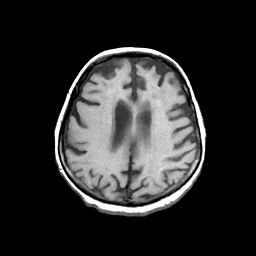

Basal Ganglia Calcification: T1-weighted MR -- Slice #12

[Home][Help][Clinical] Slice 12